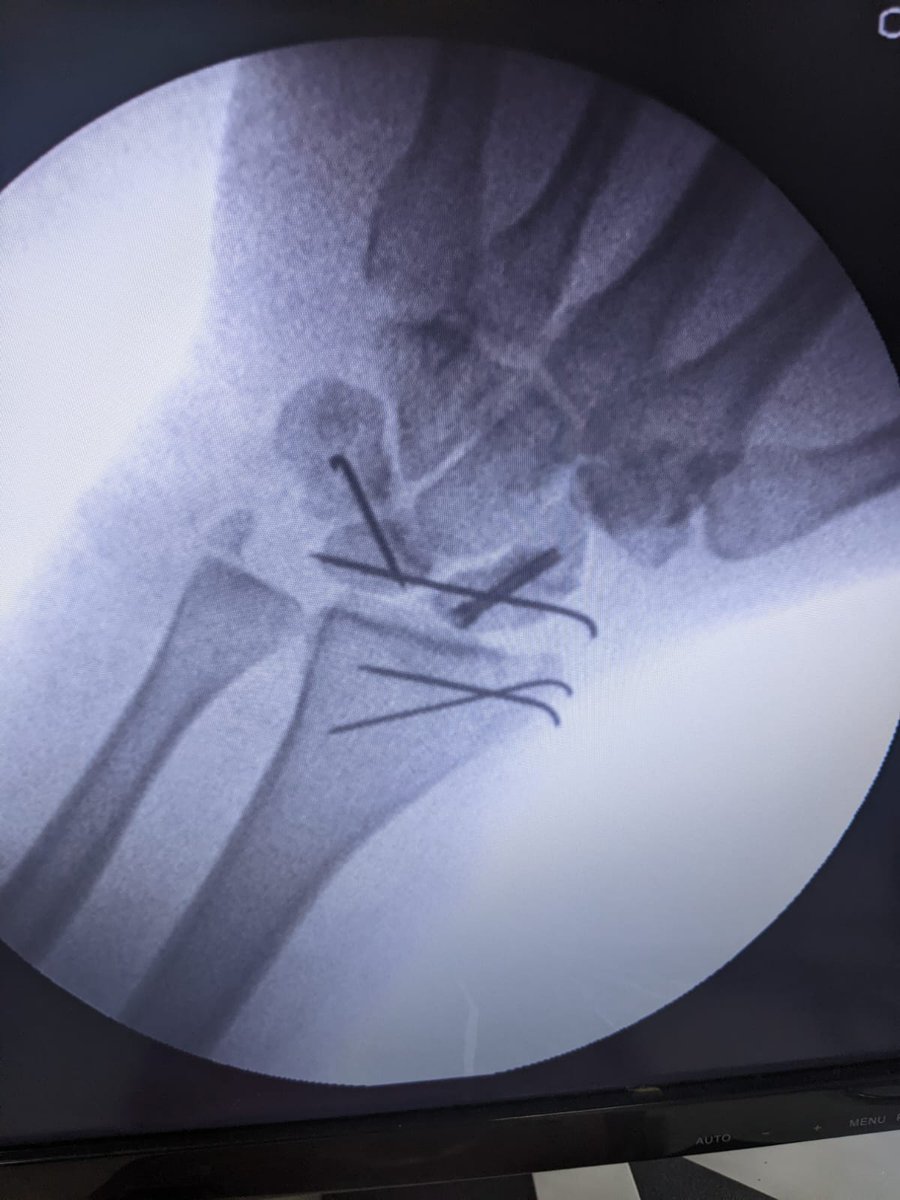

He had to be flown from Guwahati to Mumbai to undertake Surgery under Dr. Sudhir Warrier to save his left hand from life long disability. He had 5 wires and a plate inserted in left hand with 2 fingers under doubt @bhash@OlaElectric (3/n)